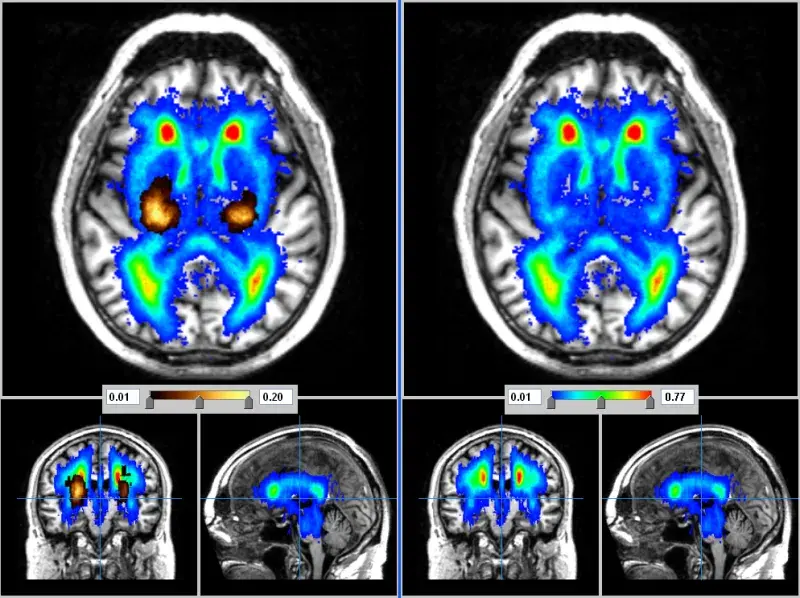

£400 could provide a short MRI scan for a research participant

• MRI scans are often used in neurological research studies because they are safe and painless for the participant, and can show doctors and scientists an incredible amount of information about the brain.

£800 could provide more detailed MRI scan for a research participant

• Specialised scans play a crucial role in developing image analysis methods by using more detailed medical images. Yet, some scans take longer time and cost more.